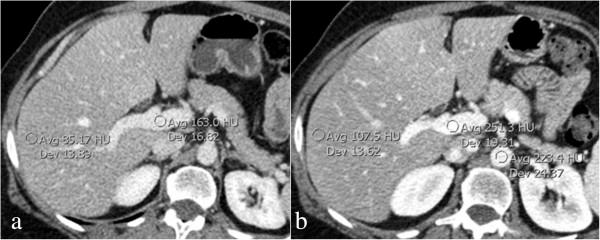

We describe a case of focal nodular hyperplasia of the liver in a 53-year-old Caucasian woman (weight 75Kg) with a colorectal adenocarcinoma histologically confirmed. An innovative split-bolus multidetector-row computed tomography technique was used that, by splitting intravenous contrast material in two boli, combined two phases (hepatic arterial phase and portal venous phase) in a single pass; a delayed (5 minutes) phase was obtained to compare the findings with that of triphasic multidetector-row computed tomography.

Split-bolus multidetector-row computed tomography was able to show the same appearance of the lesion as the triphasic multidetector-row computed tomography technique.This is the first case demonstrating the effectiveness of the split-bolus multidetector-row computed tomography technique in the detection and characterization of focal nodular hyperplasia with a significant reduction in radiation dose to the patient with respect to triphasic multidetector-row computed tomography technique.

我们描述了一名53岁白人女性(体重75千克)肝局灶性结节性增生的病例,其结直肠癌已通过组织学确诊。采用了一种创新的双期团注多排螺旋计算机断层扫描技术,该技术通过将静脉造影剂分成两团注,在单次扫描中合并了两个期相(肝动脉期和门静脉期);还获得了延迟(5分钟)期相,以便将结果与三期多排螺旋计算机断层扫描的结果进行比较。

双期团注多排螺旋计算机断层扫描能够显示与三期多排螺旋计算机断层扫描技术相同的病变表现。这是首例证明双期团注多排螺旋计算机断层扫描技术在肝局灶性结节性增生检测和特征分析中有效性的病例,与三期多排螺旋计算机断层扫描技术相比,显著降低了患者所接受的辐射剂量。